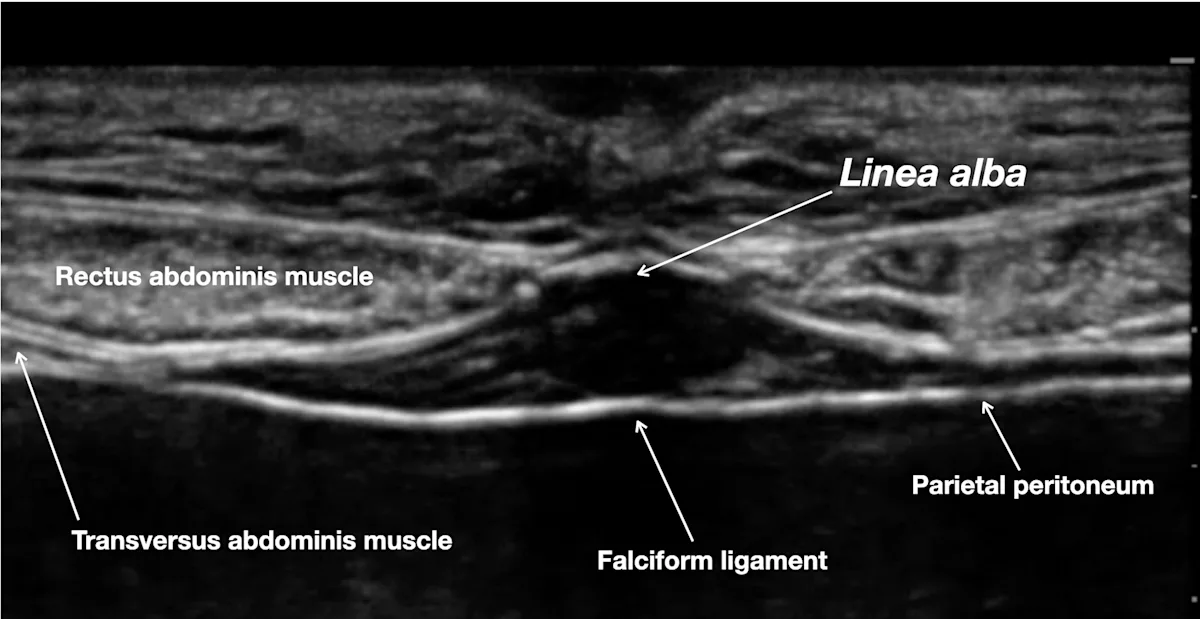

Step 6: Visualize the Abdominal Wall via Ultrasound

Position the ultrasound transducer on the cranial abdomen over the midline. Adjust the ultrasound depth and gain to obtain a clear image of the abdominal wall.

Author Insight

The linea alba, falciform ligament, parietal peritoneum, and rectus abdominis muscle should be visible.